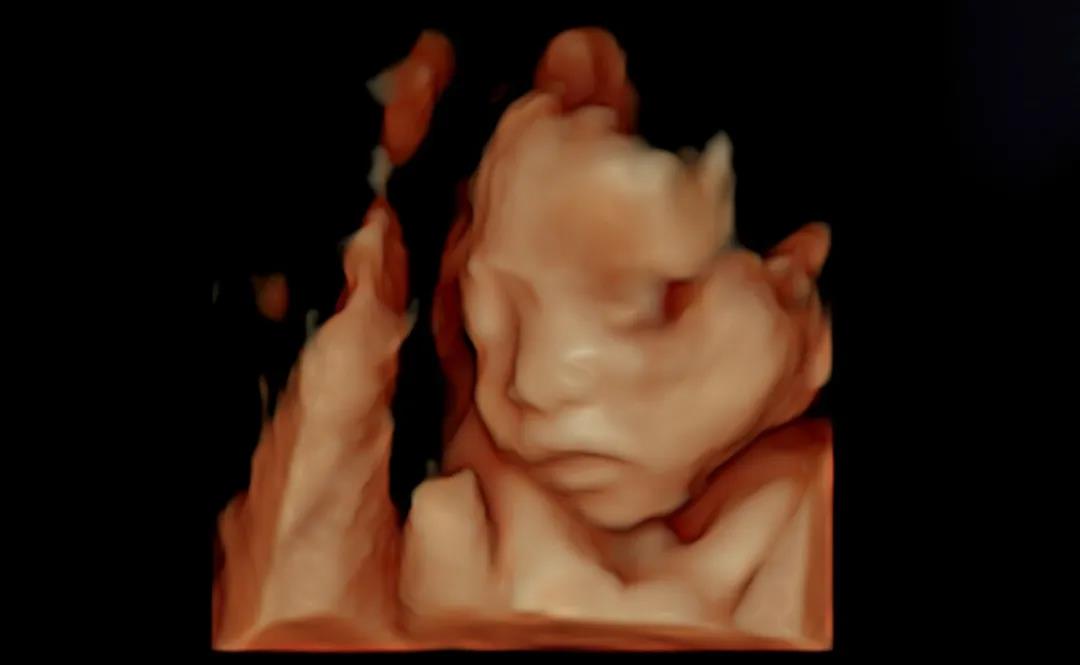

四维宝宝

瑞博医院美国GE-E10四维实机拍摄图